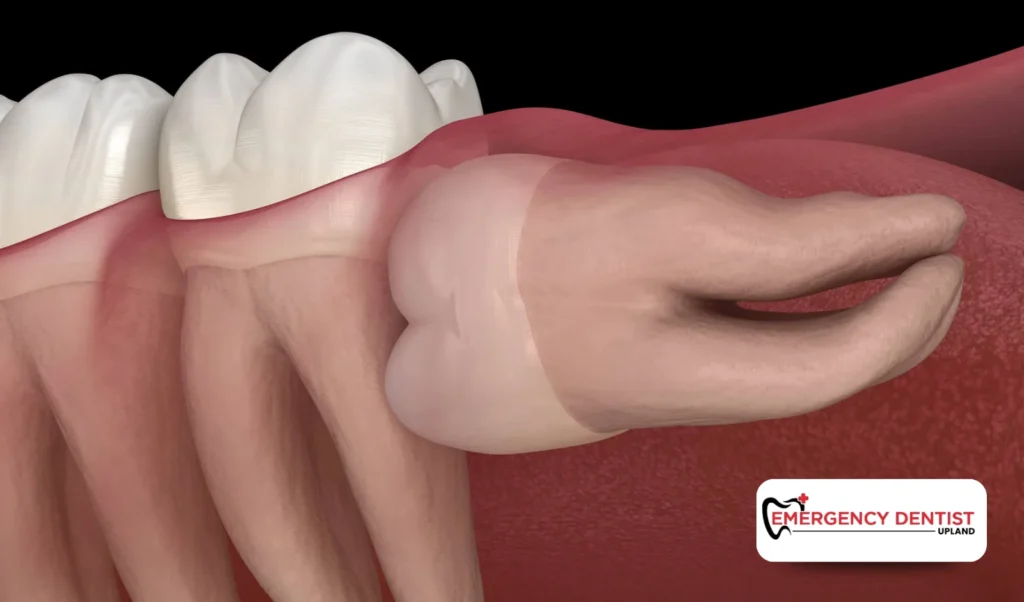

Wisdom teeth are the final molars to develop. They usually appear in the late teenage years or early adulthood. Unfortunately, the jaw often does not have enough room for them to come in properly.

When space is limited, impacted wisdom teeth may become trapped beneath the gum tissue or press against nearby molars. An impacted wisdom tooth may remain partially hidden or grow at an angle, making it difficult to clean.

- Development of fluid filled sacs around the tooth

Although wisdom teeth extraction may feel inconvenient at first, it often prevents more serious issues later. Removing impacted wisdom teeth reduces the risk of:

- Chronic gum disease

- Ongoing infection

- Damage to nearby molars

- Structural crowding

In some cases, fluid filled sacs associated with an impacted wisdom tooth can affect surrounding bone if not treated early. Addressing the issue before it worsens helps preserve your smile and overall dental stability.